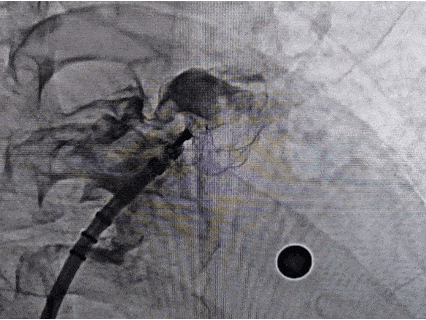

DSA下右肩位造影+测量

右肩位测量,开口22.67 mm,深度21.51 mm